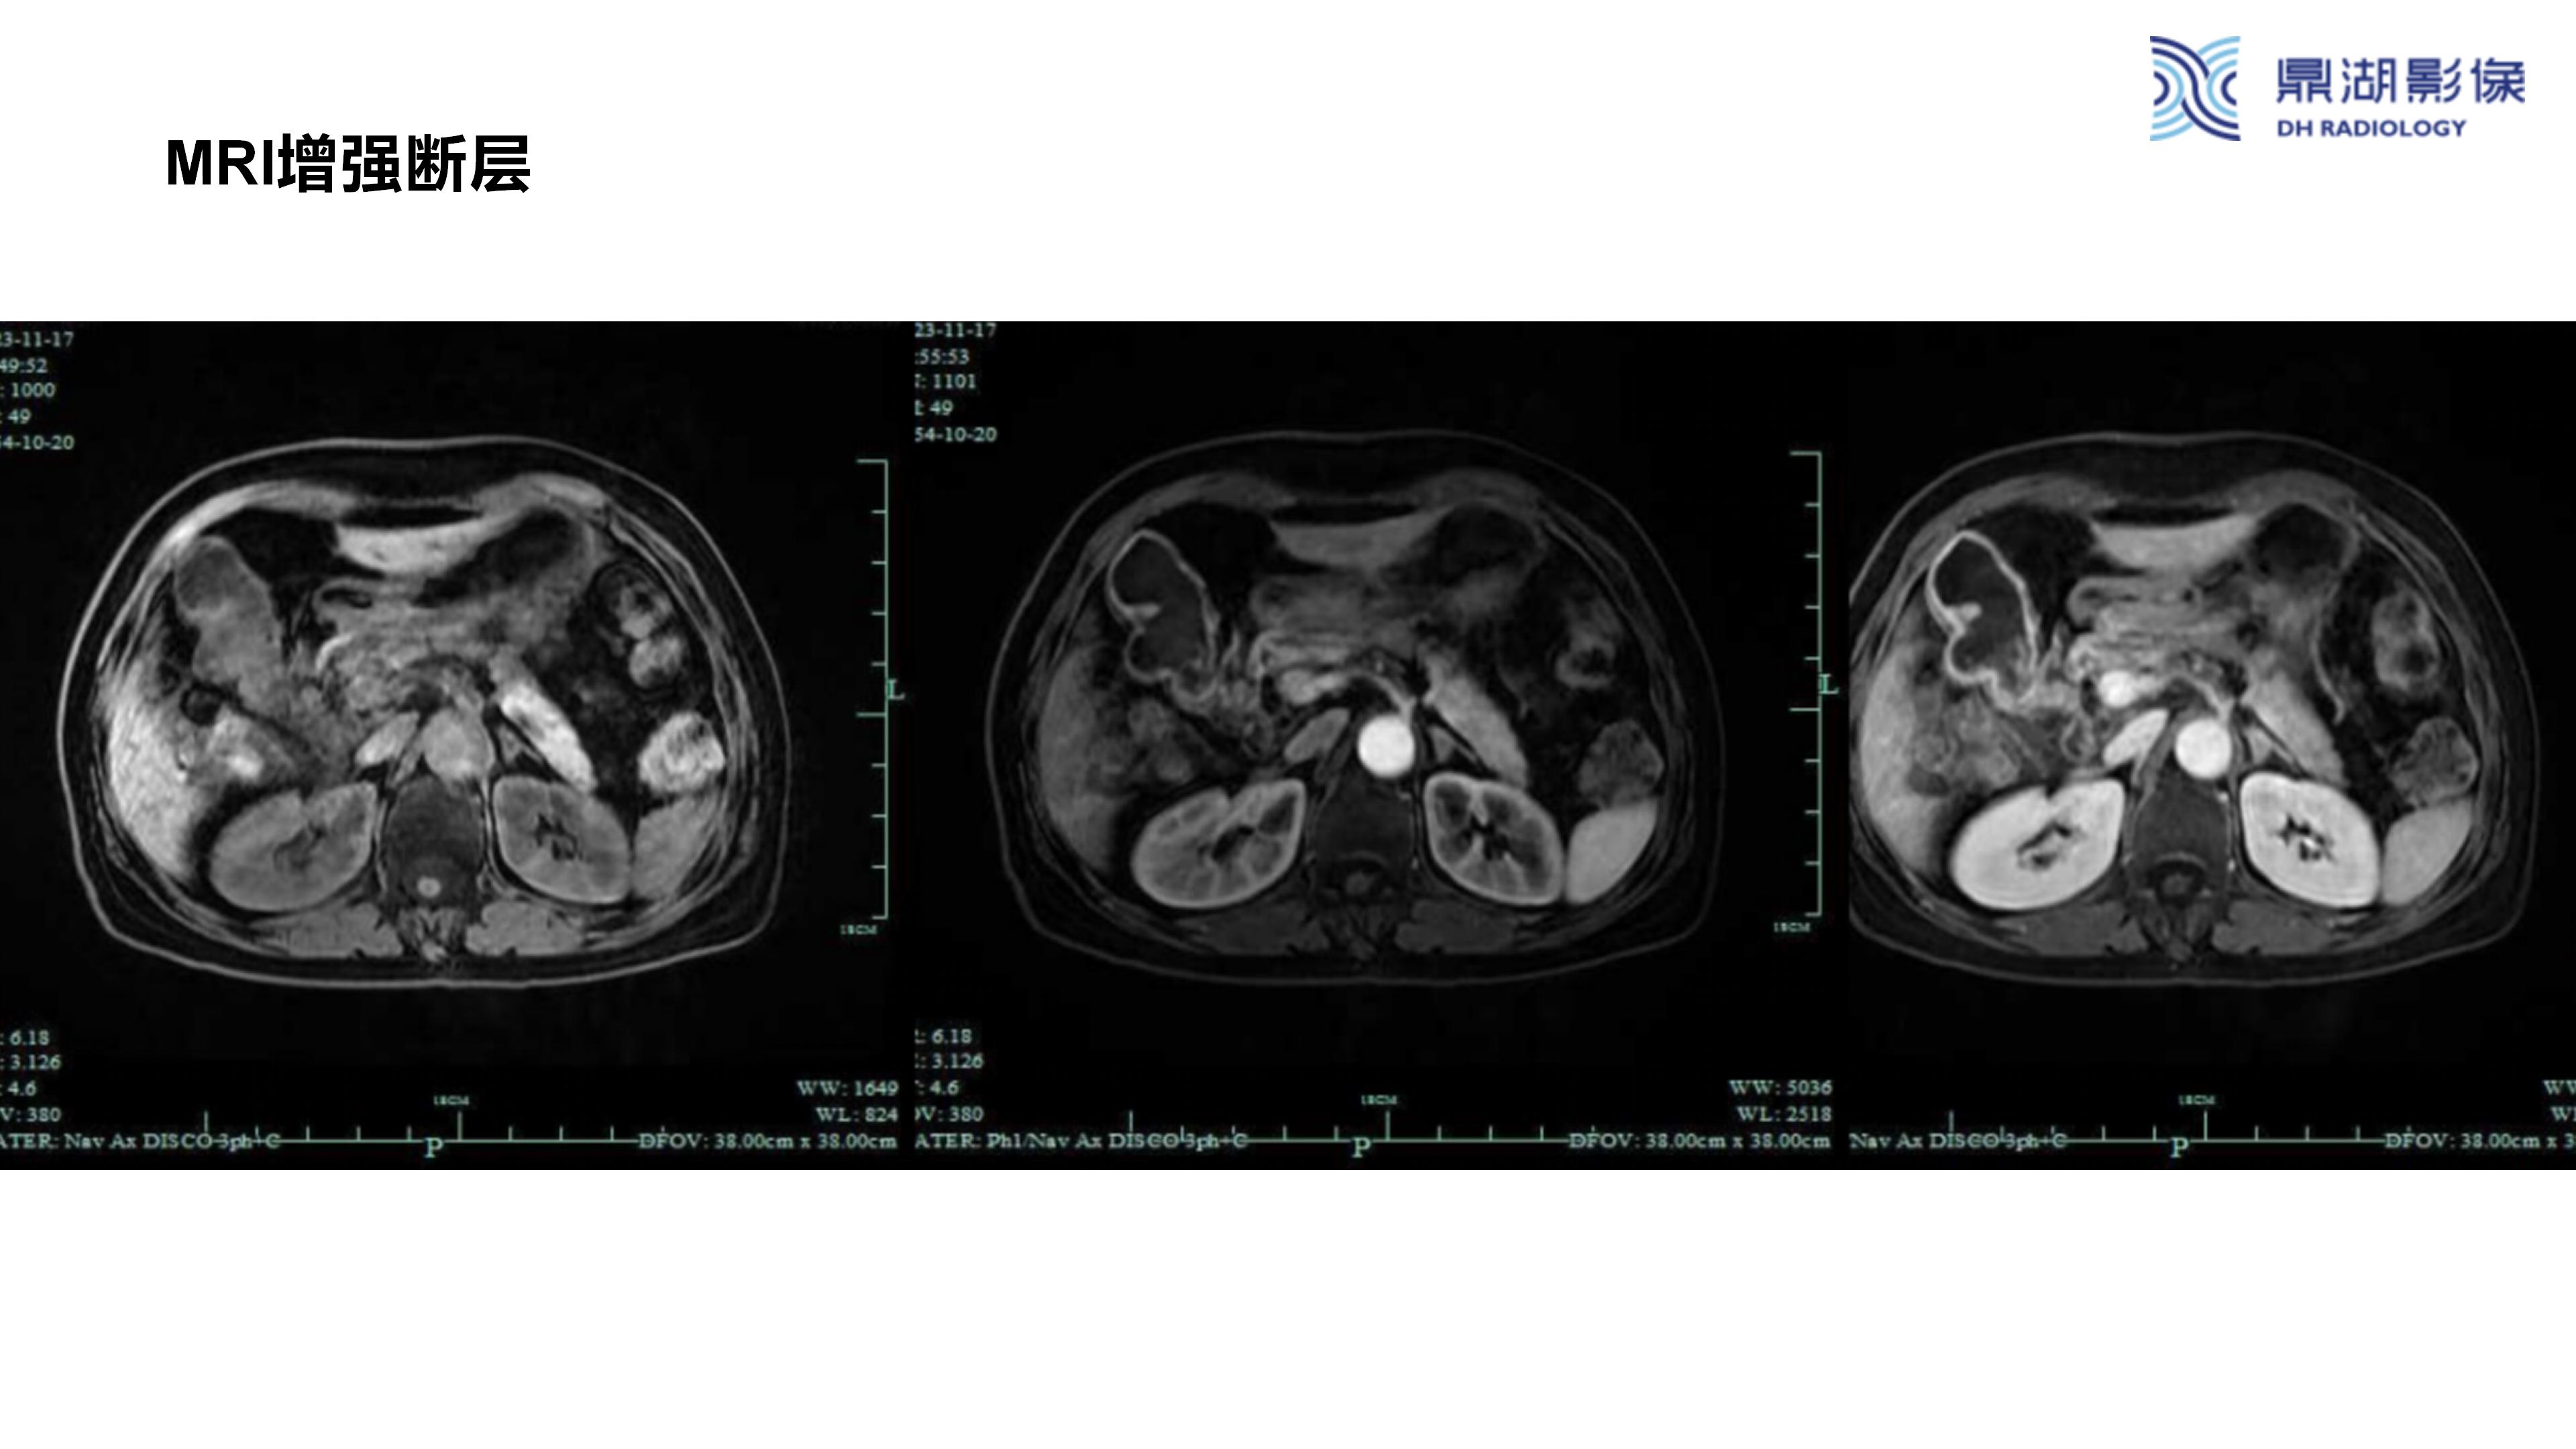

胆囊癌-鼎湖社群读片病例